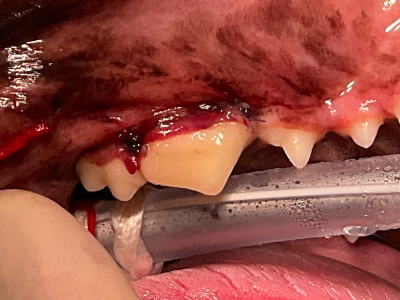

典型的な平板破折です。奥歯の先端は折れてなくなった上に、付け根部分までヒビが入っています。

歯肉の中まで割れているので、歯肉を剥離し、歯の断面と破折片をきれいに整えた後接着します。(破折片は再利用できる場合と出来ない場合があります。)